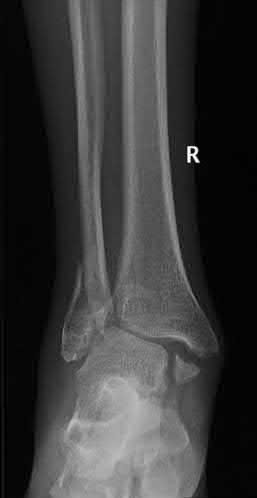

A 28-year-old male sustains a closed comminuted tibial shaft fracture.

Two hours post-injury, he develops severe leg pain unyielding to narcotics. His blood pressure is 120/80 mmHg. Intracompartmental pressure monitoring is performed. Based on current guidelines, which measurement dictates an emergent 4-compartment fasciotomy?